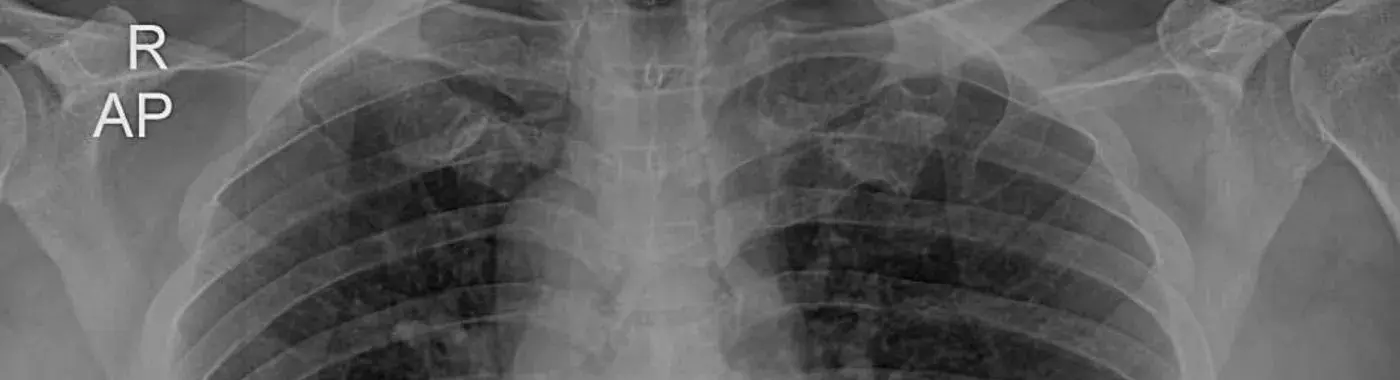

• Chest X-Ray: A chest X-ray can reveal the abnormal positioning of the heart on the right side of the chest. This may prompt further investigation into the position of other internal organs.

• Echocardiogram: An echocardiogram (ultrasound of the heart) is used to visualize the heart’s function and structure. It is often performed to rule out any congenital heart defects that may accompany dextrocardia.

• CT Scan or MRI: In some cases, doctors may order a CT scan or MRI to get detailed images of the internal organs and assess the degree of situs inversus and any associated conditions.